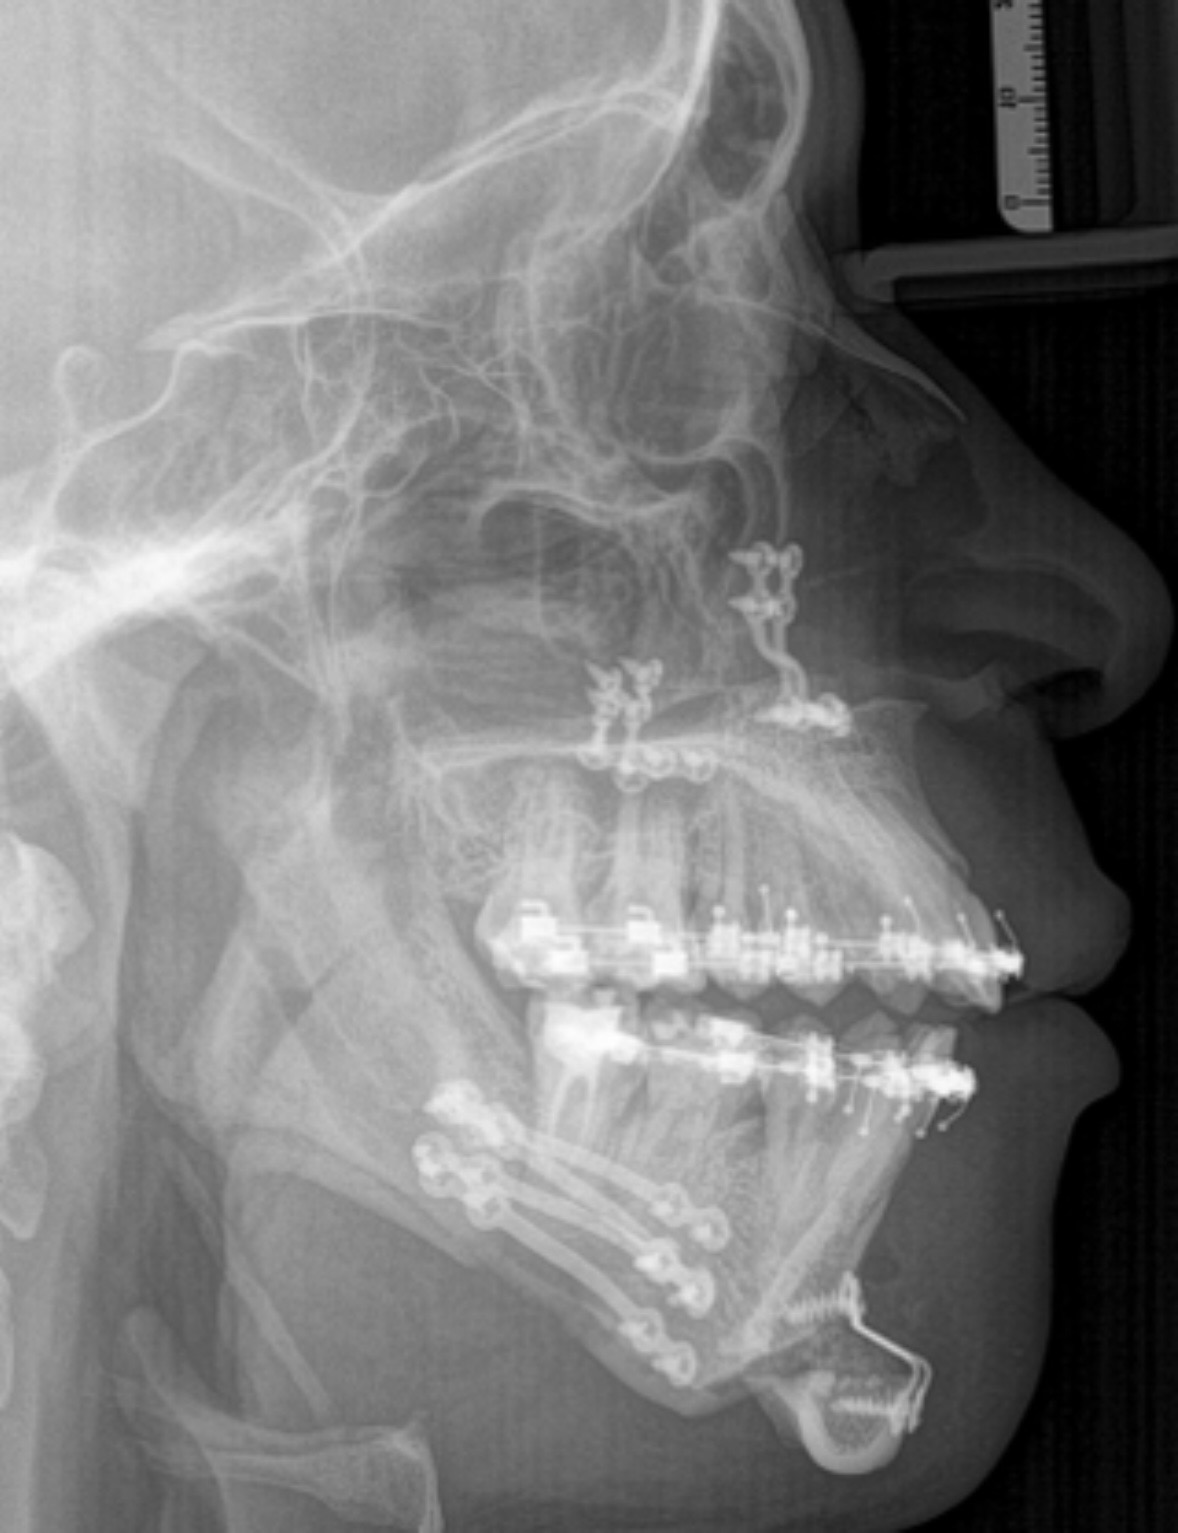

wondering if its because of too much maxilla movements or someting else like ccw

upper incisors forward movementwondering if its because of too much maxilla movements or someting else like ccw

View attachment 4715858 View attachment 4715860

is this the result of the maxilla movement or its a predisposition of the teeth being already like thatupper incisors forward movement